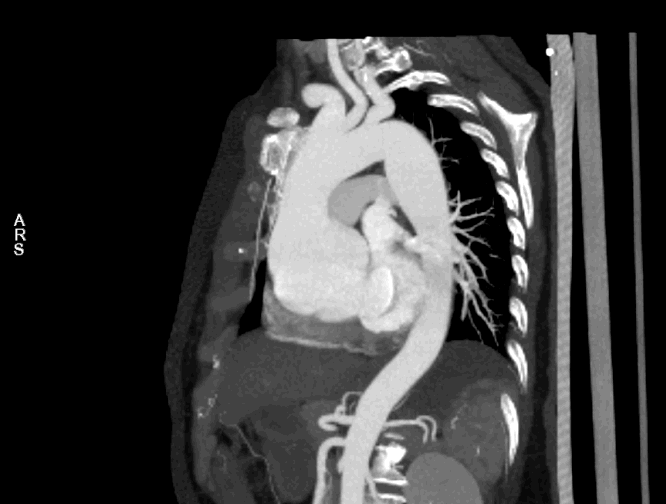

Bentall术前主动脉CTA 例1

为什么叫哈巴狗钳2023学术荟萃|王云:右侧肋间小切口体外循环心脏手术_https://www.jmylbn.com_新闻资讯_第9张

为什么叫哈巴狗钳2023学术荟萃|王云:右侧肋间小切口体外循环心脏手术_https://www.jmylbn.com_新闻资讯_第10张